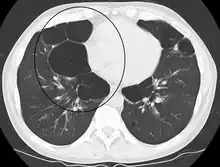

| Advanced centrilobular emphysema showing total lobule involvement on the left side | |

Centrilobular

Centrilobular emphysema, also called centriacinar emphysema, affects the centre of a pulmonary lobule (centrilobular) in the lung, the area around the terminal bronchiole and the first respiratory bronchiole, and can be seen on imaging as an area around the tip of the visible pulmonary artery. Centrilobular emphysema is the most common type usually associated with smoking, and with chronic bronchitis.[17] The disease progresses from the centrilobular portion, leaving the lung parenchyma in the surrounding (perilobular) region preserved.[24] Usually the upper lobes of the lungs are affected.[17]